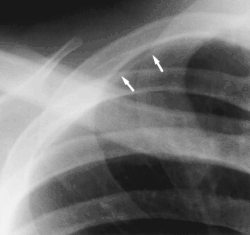

- Clavicular companion shadow is a thin soft-tissue stripe along the upper edge of the clavicle.[1]

Companion shadow

Companion shadow is a term used in describing radiographs that denotes the appearance of a smooth, homogenous, radiodensity with a well-defined margin that runs parallel with a bony landmark. Companion shadows represent soft tissue that overlies the respective bony landmark in profile. They are not seen in every radiograph and can be misinterpreted as pathology.